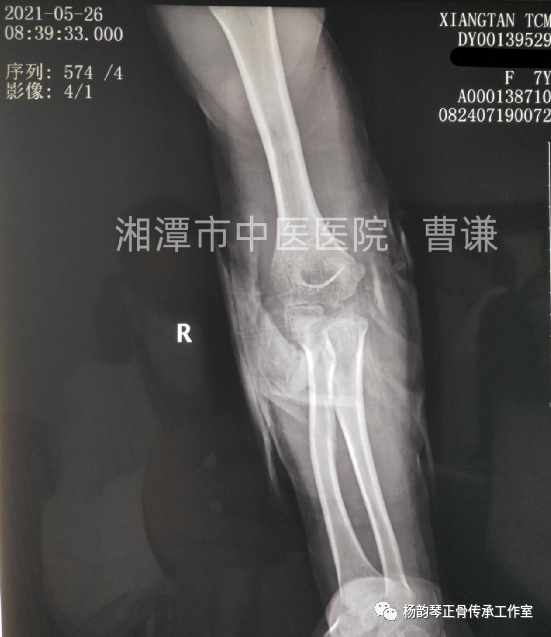

入院后予以手法复位,小夹板外固定,拍片复查示骨折对位对线良好,桡骨头脱位已纠正。具体复位手法:术者一手拇指先摸清桡骨头位置,将拇指置于肘前方,然后另一手握前臂置于前臂旋后位,再极度屈肘,拇指卡于肱骨与桡骨之间形成杠杆,通过极度屈肘促使桡骨头复位。用锐角托板固定于患肢屈肘60°(邻肢夹角法)前臂旋后位。

伤后半月余复查骨折对位对线良好,肱桡关节匹配良好,改直角托板固定,每次换药进行被动肘关节屈伸锻炼,这样有利于促进关节功能早期恢复。